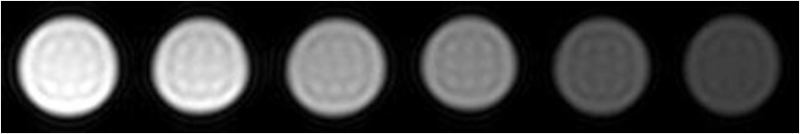

´ÅÐÔÄÉÃײÄÁÏ×÷Ϊ´Å¹²Õñ£¨MRI£©ÔìÓ°¼ÁµÄÓ¦ÓÃ